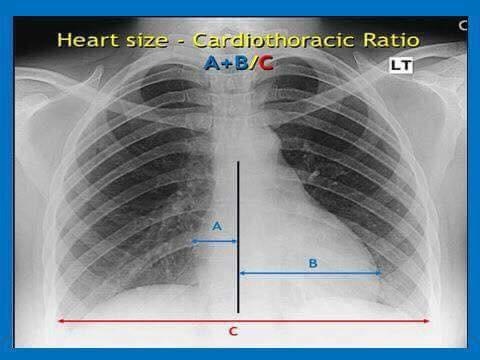

Para una radiografía del pecho, se suelen tomar dos vistas. Primero, usted se mantiene de pie con el pecho contra la película radiográfica y la imagen se toma desde la espalda. Los brazos estarán a ambos lados. Luego se suele tomar una vista lateral con los brazos por encima de la cabeza o en frente suyo. El técnico le indicará cuando debe respirar profundamente y mantenerse inmóvil. Para tomar una radiografía del pecho en personas que no pueden ponerse de pie, la película se coloca debajo de ellas y la imagen se toma desde el frente.

Un tubo especial dentro de la máquina de rayos X emite un haz de radiación controlada. Los tejidos del cuerpo absorben o bloquean la radiación en diferentes grados. Los tejidos densos como los huesos bloquean la mayor parte de la radiación, pero los tejidos blandos, como la grasa o los músculos, bloquean menos radiación. Después de pasar por el cuerpo, el haz alcanza una pieza de un fragmento de película o un detector especial. Los tejidos que bloquean altas cantidades de radiación, como los huesos, aparecen como áreas blancas en un fondo negro. Los tejidos blandos bloquean menos radiación y aparecen en tonos de gris. Los órganos que contienen principalmente aire (como los pulmones) aparecen en negro. Los tumores son por lo general más densos que el tejido que los rodea, por lo que suelen verse en tonos grises más claros.